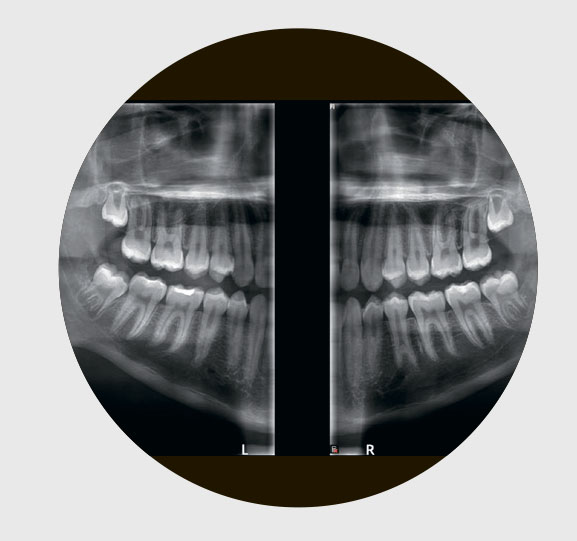

Во всех клиниках доступны внутриротовая диагностика, панорамные и томографические исследования. Единая база данных позволяет врачам быстро получать доступ к любому исследованию и при необходимости оперативно проводить консилиум. Это помогает не только точнее ставить диагноз и выстраивать оптимальный план лечения, но и контролировать результаты. Для некоторых страховых компаний это обязательное требование, для нас же — залог качества работы.

— Качество изображения в стоматологии решает все. Если снимок мутный или есть наложения слоев, врачу приходится напрягать зрение, перепроверять, отправлять пациента на дополнительные снимки. Мы даже использовали ИИ, чтобы уточнить детали на изображении.

А для врачей стало еще удобнее: все 2D-и 3D-изображения хранятся в одной карточке пациента, доступ к ним моментальный. Раньше приходилось загружать разные программы, тратить время на поиск исследований. С новым аппаратом это в прошлом. Можно сказать, что теперь наше стоматологическое зрение стало стопроцентным.

CS 8100 формирует изображения впечатляющей четкости и контрастности благодаря новым алгоритмам Tomosharp и передовым технологиям обработки снимков.